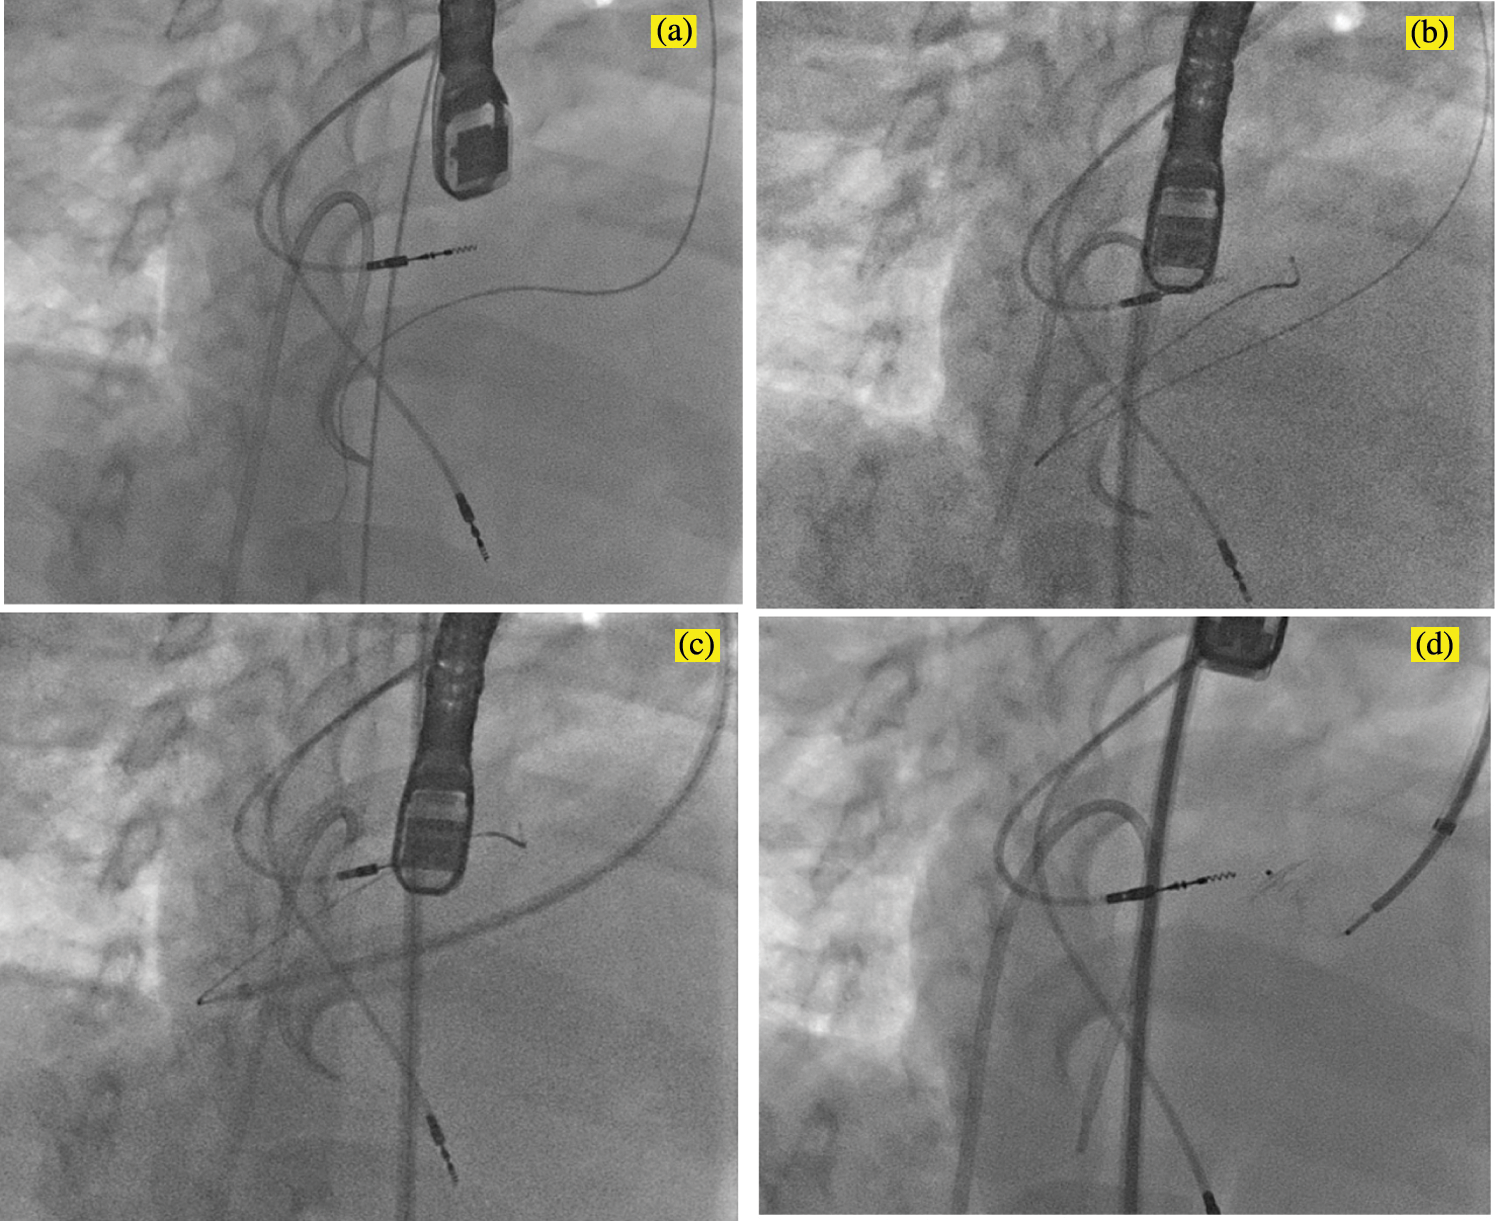

For a number of reasons, this approach was challenging in this patient. The VSD was remote from the aortic valve and could not be engaged using a Judkins coronary catheter. Instead, an Amplatz left 1 (AL-1) catheter (Cook Medical, Bloomington, IN, USA) was used to engage the defect under fluoroscopic guidance and confirmed on TEE. The floppy J-tip of the wire would not pass cleanly. The wire buckled and forced the catheter out of position even when the VSD was cleanly engaged on fluoroscopy and TEE. Instead, a 0.035 inch angle-tipped hydrophilic glide wire (Terumo Corp, Elkton, MD, USA) was selected and directed across the defect without incident (Fig. 2a). The AL-1 catheter tracked over this wire into the subpulmonary LV. Rather than forming a veno-arterial loop, we decided to utilize a retrograde deployment of an ADOII device. To do this, we exchanged the catheter and wire for a 0.035 inch Rosen guidewire (Cook Medical, Bloomington, IN, USA), and with some manipulation of the coronary catheter, we were able to achieve a redundant loop of wire in the LV cavity (Fig. 2b). A TorqVue delivery system tracked retrograde over the wire and through the defect without issue (Fig. 2c). Under a combination of fluoroscopic and TEE guidance, the device was unsheathed and then deployed. Initially, the device would not pull back cleanly to appose the septum, which we determined was due to it being trapped in the mitral valve apparatus. The device was re-sheathed without difficulty, and the left ventricular disc was opened closer to the septum. The partially unsheathed device and delivery system were pulled back as a unit without difficulty until flush against the septal wall. The rest of the device was unsheathed and appeared to be in a good position vis the septum (Fig. 2d). There was no hemodynamic derangement, and the patient remained in his usual paced rhythm without issue. After TEE and fluoroscopic inspection, the device was released. It reoriented once released from its delivery cable but remained in a good position (Fig. 3).

Figure 2: Fluoroscopic images in an RAO/Cranial projection demonstrating the steps of the VSD device closure. (a) An Amplatz Left-1 catheter was used to direct a 0.035 inch angle-tipped Terumo glide wire retrograde across the defect. The catheter was advanced cleanly across the defect without incident and used to form a redundant loop in the subpulmonary LV with a 0.035 inch Rosen guide wire (b). A TorqVue delivery system was advanced across the VSD and positioned in the LV retrograde over the Rosen wire (c). The device was then unsheathed (d); note that the RV disc is deformed due to the stiffness of the delivery cable despite no tension on the cable. LV, left ventricle; RV, right ventricle; VSD, ventricular septal defect